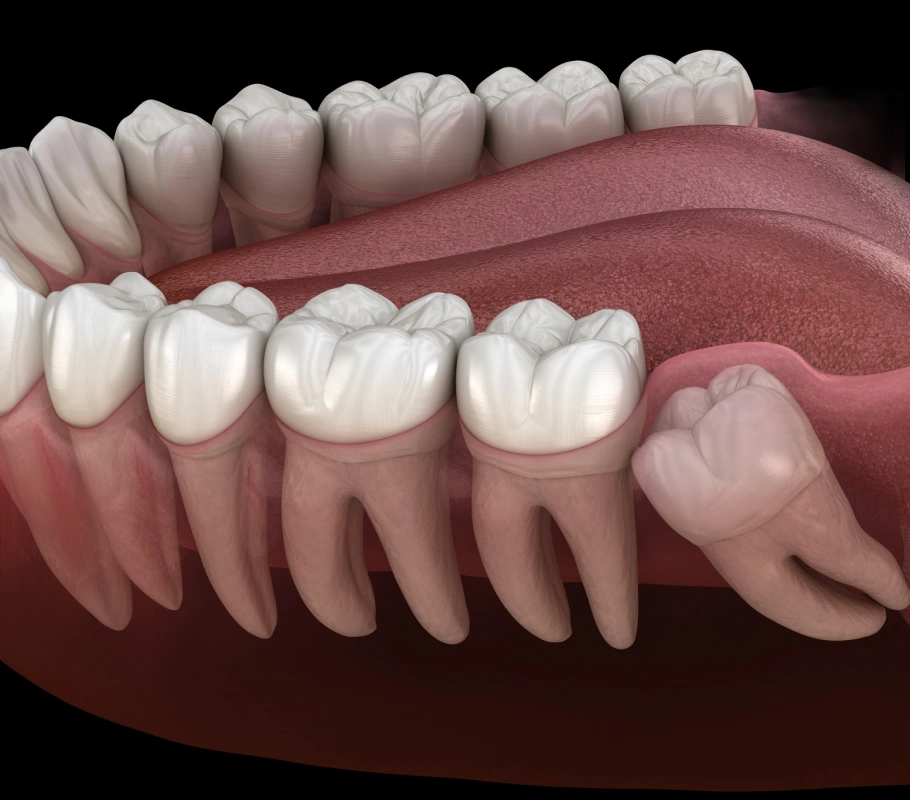

Wisdom Teeth Extraction

Get rid of bite issues and discomfort with painless wisdom tooth extraction.

Relieve Toothache With Wisdom Tooth Extraction

Why Wisdom Teeth Extraction?

If your wisdom teeth are causing pain, infection, crowding, or damage to adjacent teeth or gums, extraction may be necessary.

Wisdom Tooth Extraction Procedure

The extraction procedure can be performed under local anesthesia or sedation, depending on your preference and the complexity of the extraction.